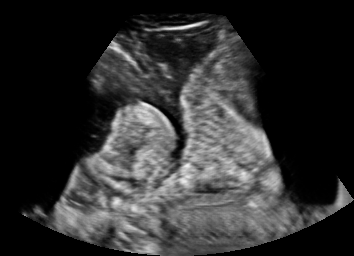

Real in-vivo images. 22 ultrasound sequences were collected using a GE Voluson E8 machine during standard fetal screening exams of 8 patients. Each sequence is several seconds long. We extracted all 4427 frames and resize them to , see Fig. 2 for some examples. The resulting image set was randomly split into training-validation-test sets by a 80-10-10% ratio.